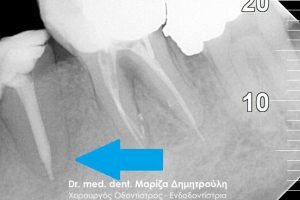

2. Ύπαρξη αλλοίωσης/ φλεγμονής γύρω από τη ρίζα. O οδοντίατρος θα πρέπει να ελέγξει αν το δόντι που έσπασε εμφανίζει στο άκρο της ρίζας του κάποια φλεγμονή ή υπάρχει κάποια αλλοίωση στο οστό γύρω από το δόντι (περιοδοντική αλλοίωση).

3. Την ποιότητα της απονεύρωσης του δοντιού, αν το δόντι που έσπασε είχε απονεύρωση. Σε περίπτωση που η ρίζα του δοντιού μπορεί να σωθεί και η παλιά απονεύρωση του δοντιού δεν καλύπτει όλο το μήκος της ρίζας του δοντιού, τότε είναι απαραίτητη η επανάληψη της απονεύρωσης για μία καλύτερη πρόγνωση του περιστατικού.